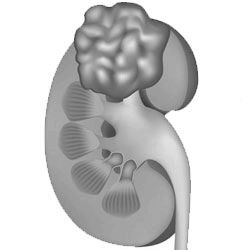

У кожному п'ятому випадку недуга передається пацієнту у спадок. Якщо протягом патології ускладнене захворюванням Бурневіля-Прінла, то це значною мірою ускладнює лікування пацієнтів. Однак, навіть без ускладнень пухлина таїть в собі небезпеку для організму. Оскільки в новоутворення входять кровоносні судини, то це створює постійну загрозу розриву пухлини і крововиливи в заочеревинного простору. У ряді випадків клітини гладеньких м'язів перероджуються і замінюються сполучною тканиною, що робить пухлина більш щільною. При цьому тканина починає випинатися крізь мережу кровоносних судин, а сама ангіоміоліпома стає схожою на виноградне гроно. Поява цих змін робить пухлина вразливою до розривів і перфорації стінок.

Сама по собі пухлина не є злоякісної і не дає метастази, однак її зростання може значно поміщати функціонуванню органу-господаря. Найбільш поширені проблеми, які приносить ангіоміоліпома нирки, - це проростання в клітковину, лімфовузли, нижню порожнисту вену і інші судини.

Найчастіше ангіоміоліпома локалізується в мозковій або кірковому шарі нирки і відмежована від органу капсулою. Як правило, новоутворення виникає з одного боку, а ось множинні ураження нирки зустрічаються при туберозному склерозі.